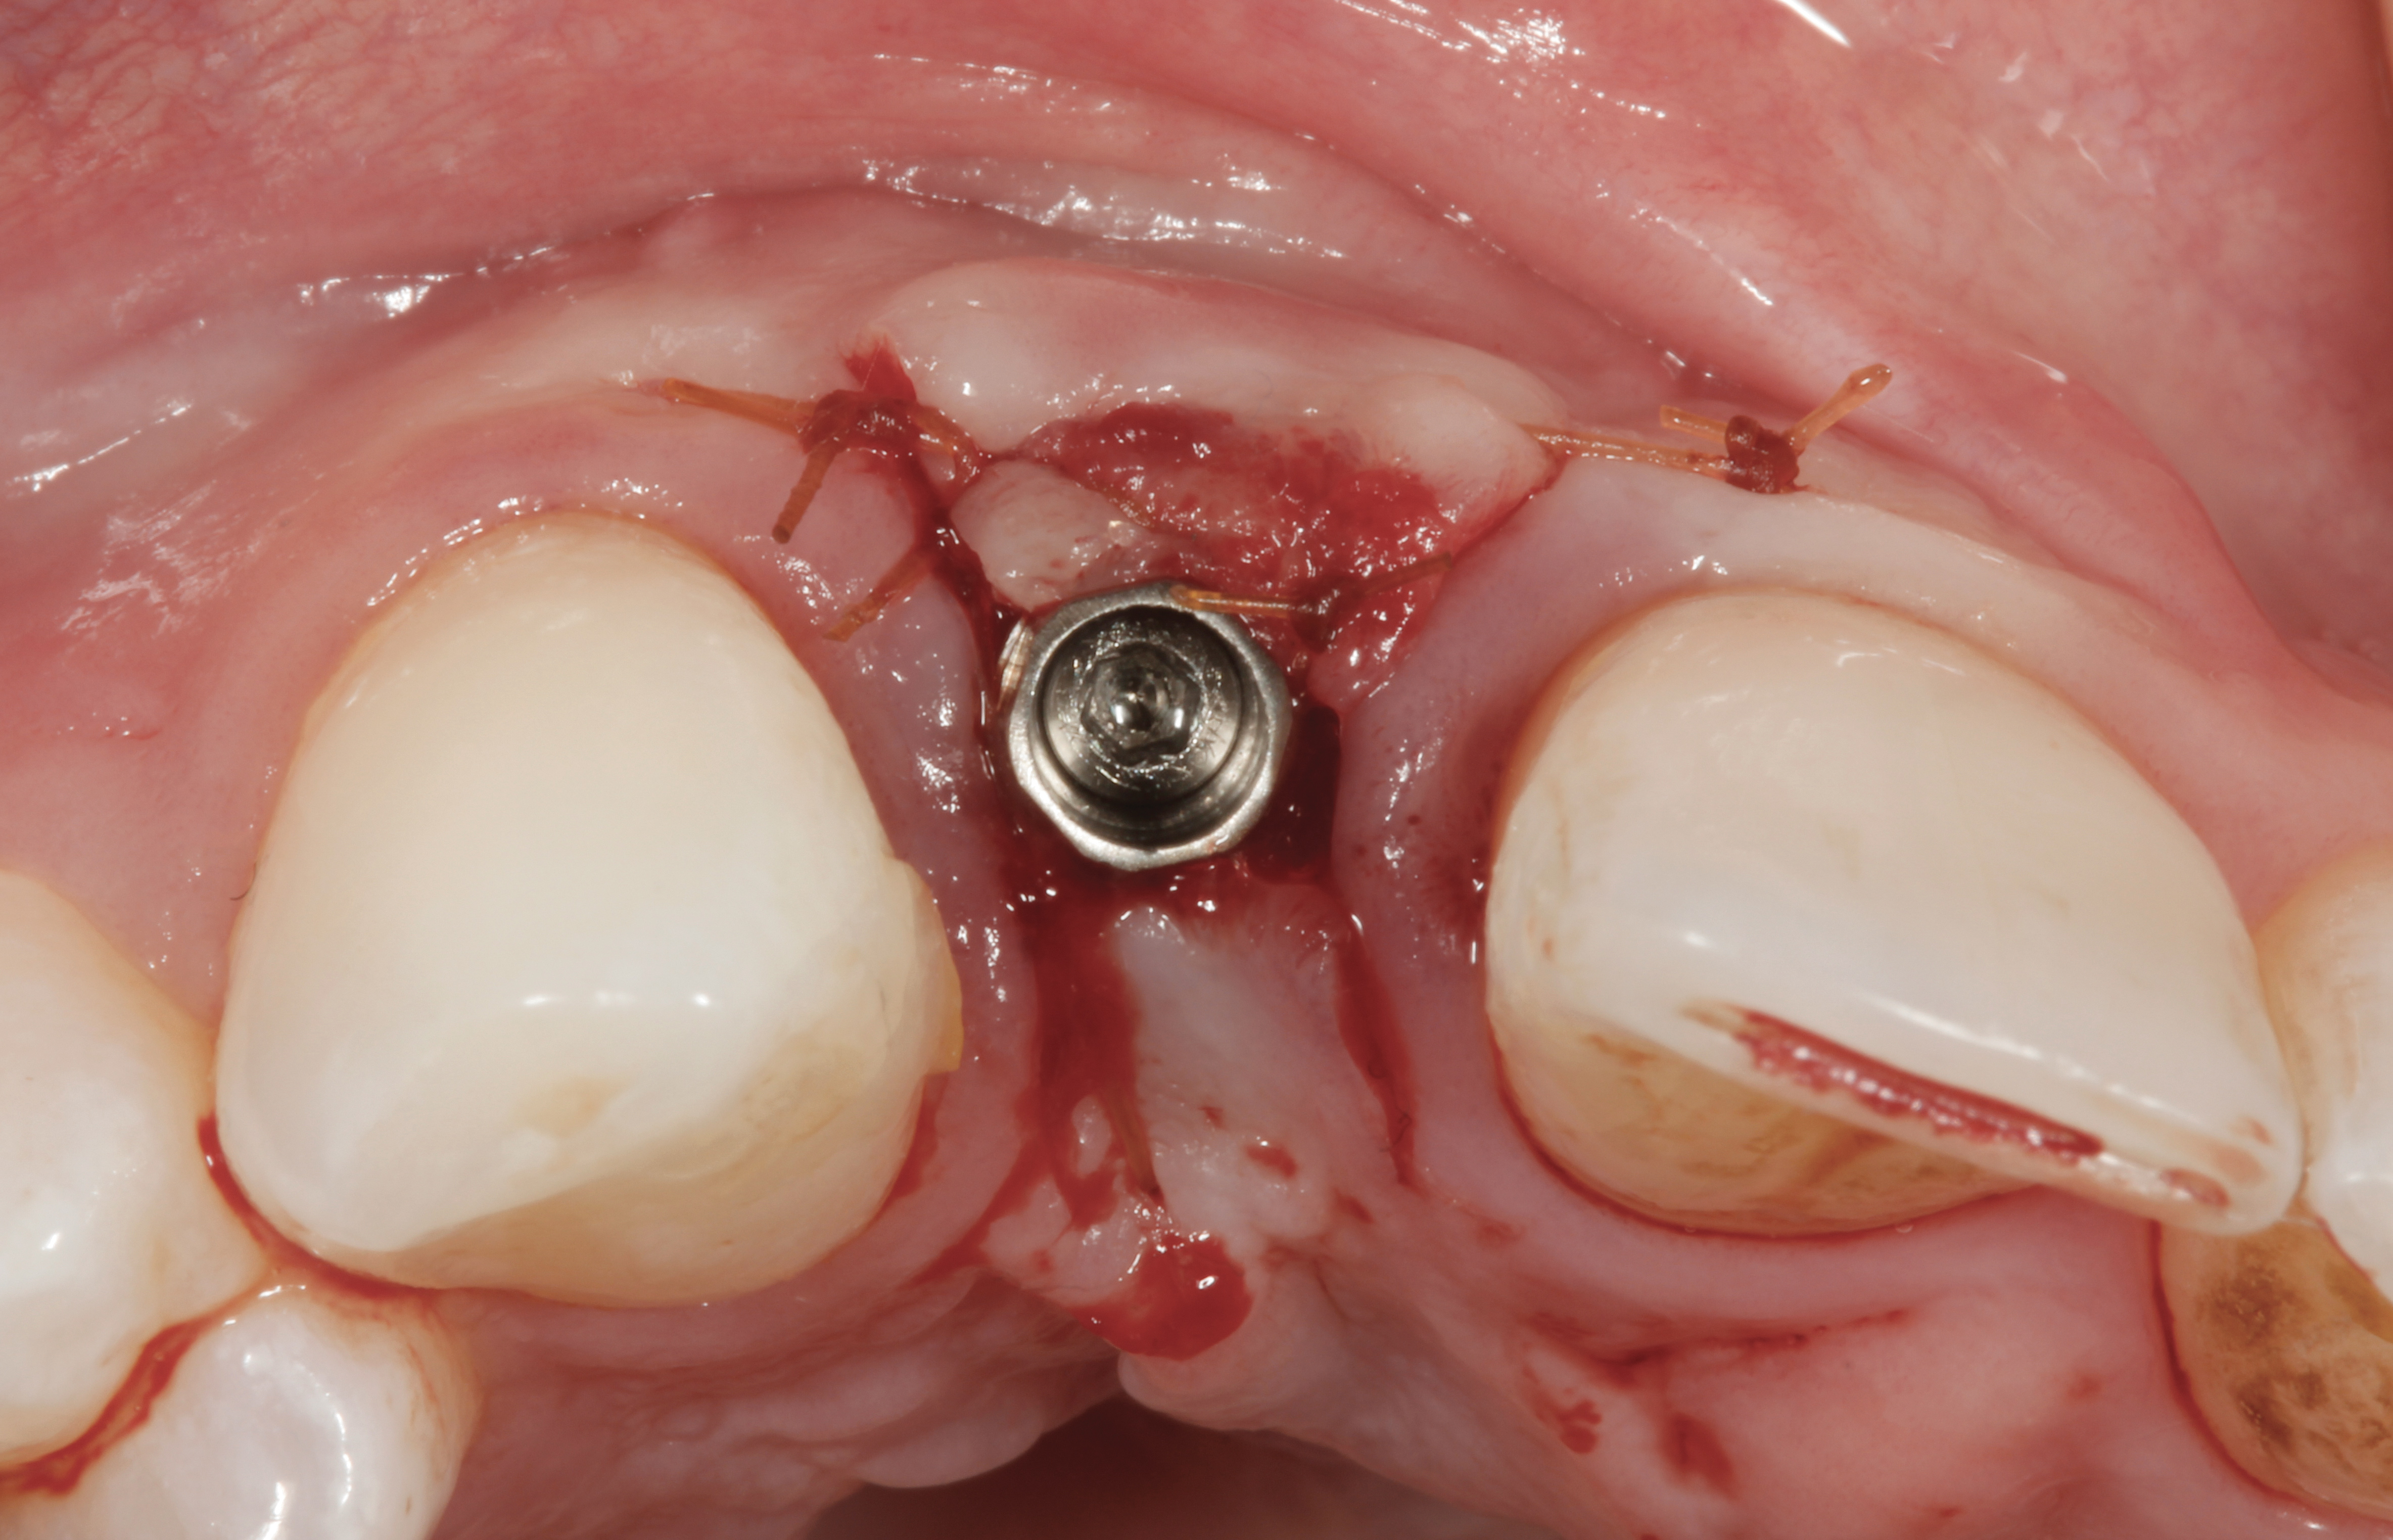

Fig 5. A surgical cover screw was placed onto the implant in order to achieve gingival augmentation in situ prior to a secondary soft-tissue procedure.

Figure 5

Fig 34. A surgical cover screw was placed in an attempt to decoronate the implant and gain soft-tissue coverage in situ.

Figure 34